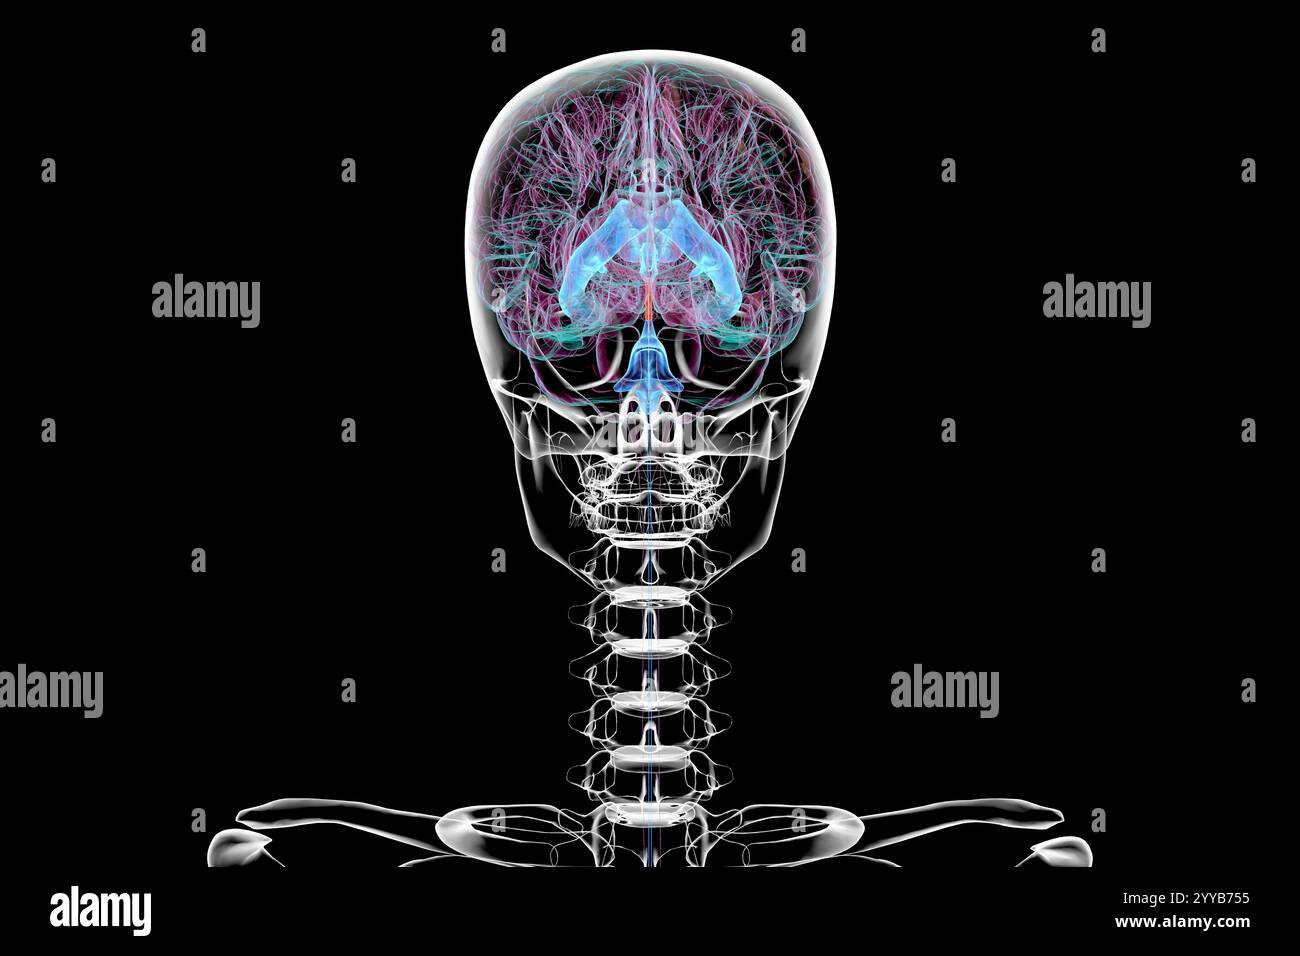

RF2YYB751–Computerdarstellung des cerebralen Aquädukts (orange), eines schmalen Kanals im Mittelhirn, der den dritten und vierten Ventrikel verbindet und den Liquorfluss erleichtert.

RF2YYB74X–Computerdarstellung des cerebralen Aquädukts (orange), eines schmalen Kanals im Mittelhirn, der den dritten und vierten Ventrikel verbindet und den Liquorfluss erleichtert.

RF2YYB75A–Computerdarstellung des cerebralen Aquädukts (orange), eines schmalen Kanals im Mittelhirn, der den dritten und vierten Ventrikel verbindet und den Liquorfluss erleichtert.

RF2YYB754–Computerdarstellung des cerebralen Aquädukts (orange), eines schmalen Kanals im Mittelhirn, der den dritten und vierten Ventrikel verbindet und den Liquorfluss erleichtert.

RF2YYB75B–Computerdarstellung des cerebralen Aquädukts (orange), eines schmalen Kanals im Mittelhirn, der den dritten und vierten Ventrikel verbindet und den Liquorfluss erleichtert.

RF2YYB759–Computerdarstellung des cerebralen Aquädukts (orange), eines schmalen Kanals im Mittelhirn, der den dritten und vierten Ventrikel verbindet und den Liquorfluss erleichtert.

RF2YYB755–Computerdarstellung des cerebralen Aquädukts (orange), eines schmalen Kanals im Mittelhirn, der den dritten und vierten Ventrikel verbindet und den Liquorfluss erleichtert. Rückansicht.

RF2YYB752–Computerdarstellung des cerebralen Aquädukts (orange), eines schmalen Kanals im Mittelhirn, der den dritten und vierten Ventrikel verbindet und den Liquorfluss erleichtert. Rückansicht.

RF2YYB75E–Computerdarstellung des cerebralen Aquädukts (orange), eines schmalen Kanals im Mittelhirn, der den dritten und vierten Ventrikel verbindet und den Liquorfluss erleichtert. Ansicht von unten.